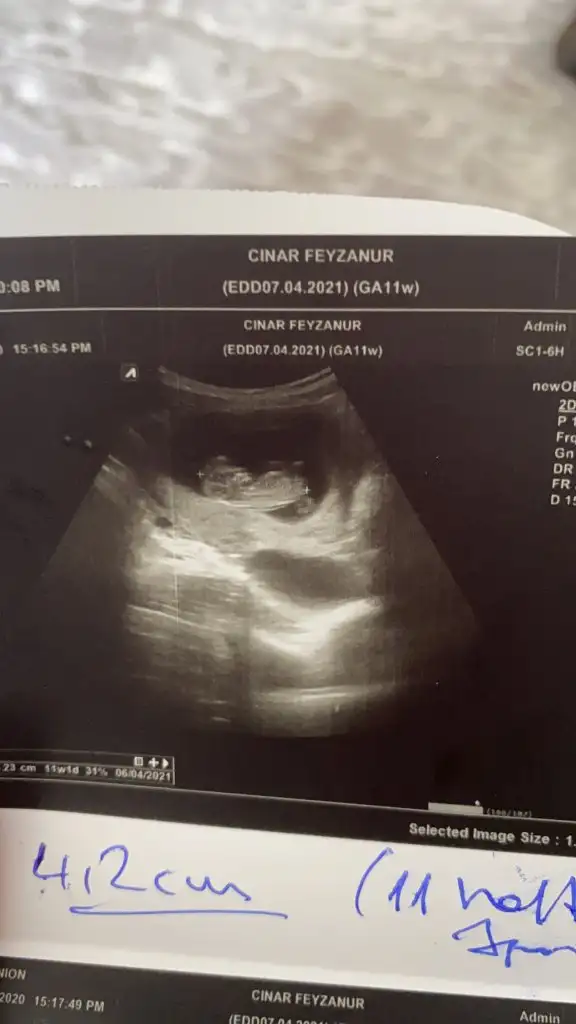

Karından bakıldı ise erkekBende yorum alabilir miyim

Karından bakıldı ise erkekHanımlar sizce

Evet karından bakıldı daha öncede atmıştım o zaman vajinaldi kız demiştiniz nubu merak ediyorum doğrusu o zamanda atarım inşallah teşekkürlerKarından bakıldı ise erkek

Evet en iyi nub Dr USG cihazı ile nasıl tutuyorsa o resmi alıyor sanırımEvet karından bakıldı daha öncede atmıştım o zaman vajinaldi kız demiştiniz nubu merak ediyorum doğrusu o zamanda atarım inşallah teşekkürler